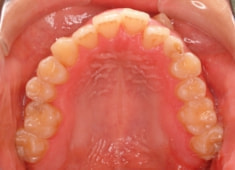

治療前

解説:残存している左上乳犬歯Cを抜歯し、そのスペースに左上3番を誘導しました。Cと犬歯ではスペースが足りないので、前歯をアドバンスさせ、反対咬合を同時に解消しております。